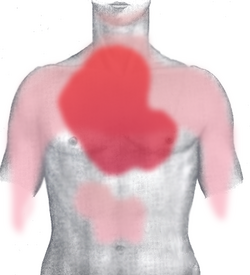

| Pain in acute myocardial infarction (rear) | self made (based upon image:Gray1211.png from Gray's Anatomy) - selbst gemacht unter Verwendung von image:Gray1211.png aus Gray's Anatomy | J. Heuser JHeuser | Datei:AMI pain back.png | |

| Pain in acute myocardial infarction (front) | self made (based upon image:Gray1219.png from Gray's Anatomy) - selbst gemacht unter Verwendung von image:Gray1219.png aus Gray's Anatomy | J. Heuser JHeuser | Datei:AMI pain front.png | |